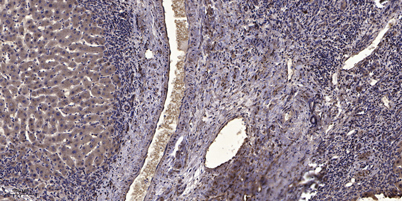

IHC

IHC-p 1:50-300